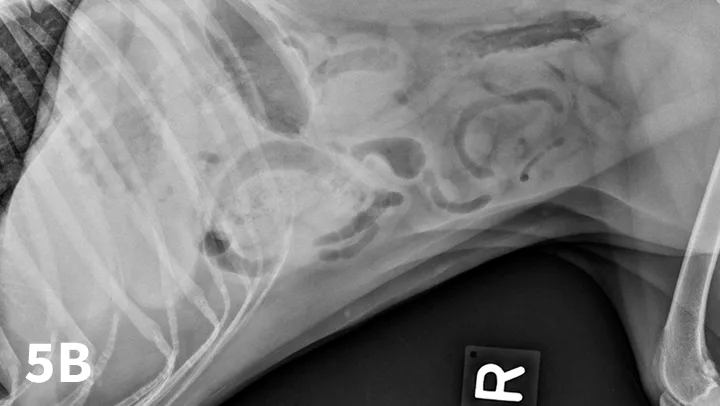

Right and left lateral abdominal radiographs are easy to obtain and are often helpful in cases of suspected GI FBs and obstruction because this positional change shifts the fluid and gas present into different areas, which might highlight potential intraluminal FBs (Figure 5). The main benefit of this simple technique is in the identification of pyloric FBs in cases of suspected pyloric outflow obstruction, but it is also useful in the small intestine, especially if duodenal FBs are suspected.

Figure 5A depicts a left lateral abdominal radiograph of a dog with a pyloric foreign body. Figure 5B depicts a right lateral abdominal radiograph of a dog with a pyloric foreign body.

Left lateral radiograph (A) of a 4-year-old crossbreed dog with a 3-day history of vomiting and anorexia. An irregularly marginated, well-defined, soft tissue opaque structure (arrows) outlined by gas is present within the pylorus on the left lateral view. A right lateral radiograph of the same dog (B). The irregularly marginated, well-defined, soft tissue opaque structure displayed in Figure 5A is not clearly seen on the right lateral view because of the dependent distribution of fluid into the pyloric antrum silhouetting with the foreign body. This was confirmed to be cloth causing a gastric outflow obstruction.